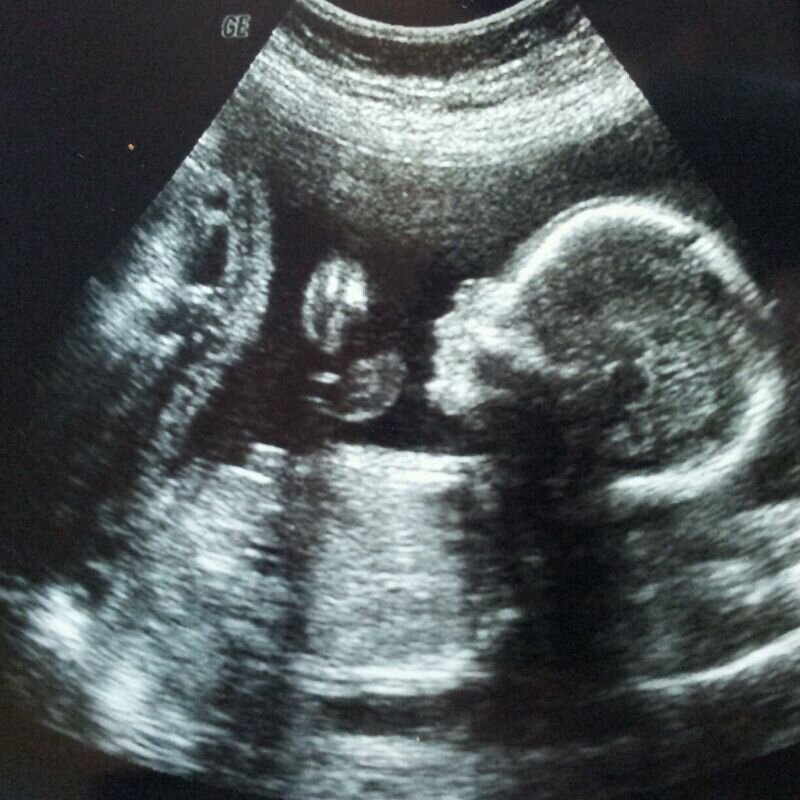

Итак, два месяца покупки тестов и ура! Мы беременны! Едим на УЗИ, чтобы точно знать. Ура! у нас будет ребенок!